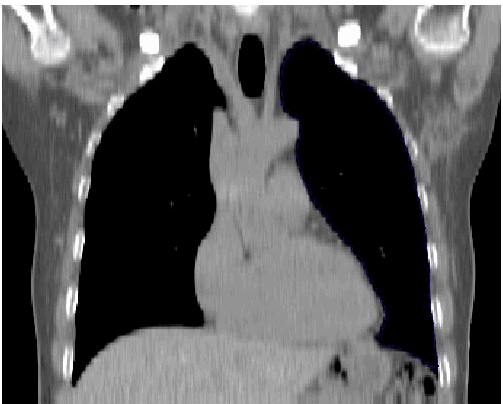

blauer Punkt In der frontalen Ebene ist die Herz Silouette durch das tiefe Zwerchfell sehr schlank!